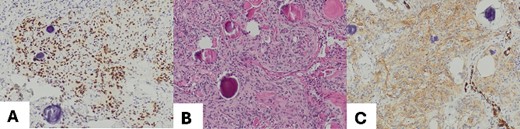

The excised tumor measured 1.5 cm in its largest dimension. Final pathology confirmed negative margins. Notably, while the initial intraoperative diagnosis based on frozen section analysis indicated a hamartoma, the subsequent comprehensive pathological evaluation revealed the presence of a transitional type of pulmonary meningioma with evidence of numerous psammoma corpuscles on microscopic examination. Further analysis showed that the tumor tested positive for epithelial membrane antigen (EMA) and progesterone (PR), with a low proliferation rate (<5%), confirming the diagnosis of a pulmonary meningioma (Fig. 2). There were no signs of abnormal cell features or increased cell division rate, which would indicate an atypical or malignant meningioma.

(A) Meningothelial cells with some psammoma corpuscles; magnification 100×; (B) Image EMA: immunohistochemical positivity for EMA, and magnification 100×; (C) progesterone image: immunohistochemical positivity for progesterone; magnification 100×.